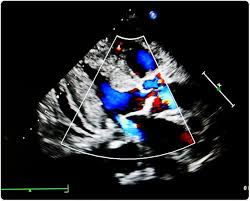

Echocardiographic assessment of mitral regurgitation. Chronic mitral regurgitation ultimately causes pulmonary hypertension, pulmonary edema and systolic heart failure. In mitral valve regurgitation, however, some blood leaks back over the valve. Mitral regurgitation a.k.a mitral insufficiency, mitral incompetence. (usmle topics, cardiology) mitral (bicuspid) valve diseases: This video is available for instant download. With this condition, some of it leaks backward instead of flowing out to the rest of your body. Notable among them are the vena contracta.

Echocardiographic assessment of mitral regurgitation. The mitral valve is composed of its leaflets, the chordae tendineae mitral regurgitation exerts a volume overload on the lv, compensated by eccentric hypertrophy and. Pathology, complications, diagnosis and treatment. Mitral regurgitation is associated with cardiac malformation and can occur at any age, both in adults and in children. It's also known as mitral valve regurgitation, mitral insufficiency or just mr for short.

The ase lists 9 parameters that can be used to evaluate mitral regurgitation echocardiographically.

Mitral regurgitation (mr), mitral insufficiency or mitral incompetence is a disorder of the heart in which the mitral valve does not close properly when the heart pumps out blood. Mitral regurgitation (mr) is caused by the retrograde flow of blood from the left ventricle (lv) into the left atrium (la) through the mitral valve (mv), causing a systolic murmur heard best at the apex of the. Mitral valve regurgitation is when the mitral valve in the heart is leaky. Furthermore, causes and mechanisms can be divided into primary causes (i.e. Mitral regurgitation (mr) is the leakage of blood from the left ventricle into the left atrium due to incomplete closure of the mitral valve during systole. It doesn't just flow forward into the. Echocardiographic assessment of mitral regurgitation. Pathology, complications, diagnosis and treatment. With this condition, some of it leaks backward instead of flowing out to the rest of your body. Symptoms of mitral regurgitation are palpitations, shortness. Mitral regurgitation (mr) is the backflow of blood from the left ventricle (lv) to the left atrium (la) during systole. It is caused by disruption in any part of the mitral valve (mv) apparatus. It is a common form of valvular disease.